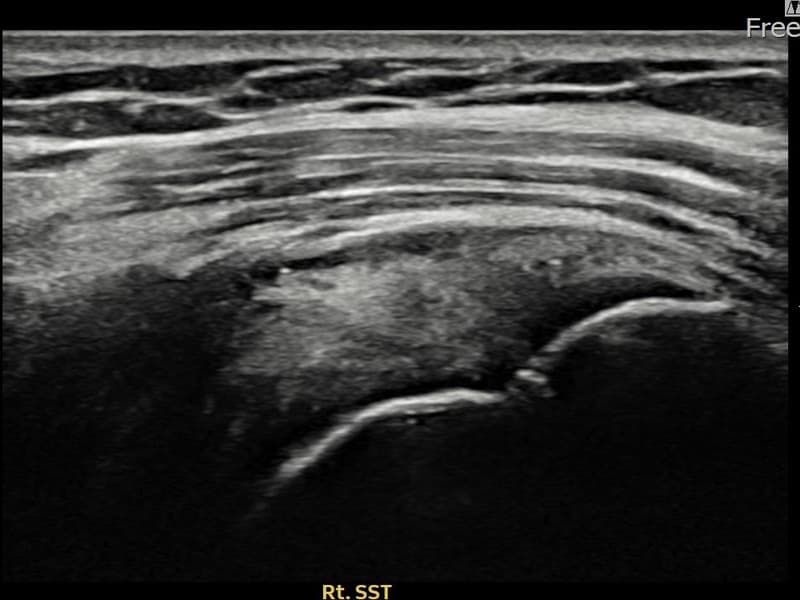

施術後

術前超音波にて右 棘上筋腱 滑液包面側部分断裂・右肩棘上筋腱のエコー不連続と腱欠損(8mm × 4mm (腱厚の約35%欠損))を確認。術後超音波では断裂部位が再生組織で充填され、腱の連続性回復とエコーパターンの正常化が確認されました。